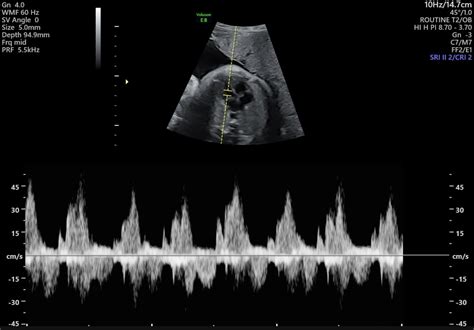

Diagnosing Hypotension in Third Trimester

Diagnosing hypotension in the third trimester involves a comprehensive evaluation by a healthcare provider. The diagnostic process typically includes:

• Blood Pressure Monitoring: Regular blood pressure checks are essential to monitor any fluctuations.